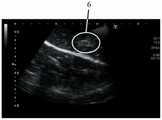

参见图2A及图2B,其显示借由具有18cm的22G针头的针刺装置注射1mL的样品A后切开的注射部位。如图2A所示,注射部位4由圆圈所表示。注射部位4显示褪色部分5,其表示由于样品A和组织之间的相互作用而引起的蛋白质变性。如图2B所示,扩散模式6由圆圈所表示。扩散模式6显示样品局限及积聚于一个区域内。借由医师所提供的结果显示,容易度/难度等级为A4,可见度等级为S3,其表明使用22G针头比18G针头更难以注射,且于超声波成像下,其成像也比18G针头来得更加不可见。于此实验中,只观察到一小滴的少量渗漏,起初可识别出来,但随后便被吸收回组织内。See Figures 2A and 2B, which show the cut injection site after injecting 1 mL of sample A by the acupuncture device with a 22G needle of 18 cm. As shown in Figure 2A, the